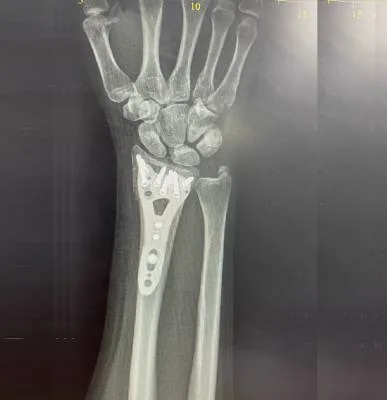

The wrist is a highly flexible and complex joint that supports hand movement and daily activities.

I went for wrist pain and Dr. Haytham Elkhatib Orthopedic treated me with utmost care and

professionalism. Even taking extra time to explain to me the diagnosis in simple terms .

Thank you so much Dr. Haytham ·